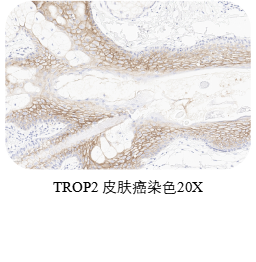

❶ 质控选择

在正常和肿瘤组织中,TROP2染色主要定位于细胞膜,部分伴有较弱的细胞质染色。扁桃体可同时作阴阳性对照,作为阳性对照,扁桃体隐窝上皮表现出较强的膜染色;作为阴性对照,除隐窝上皮外的其他区域应为阴性。选取皮肤作为阳性对照,皮肤的表皮细胞应表现出较强的膜染色。

ACRO IHC实验室目前已建立了成熟的TROP2染色方法与判读体系,适用三阴性乳腺癌、前列腺癌、胰腺癌、卵巢癌、皮肤癌等多个癌种,可快速用于相关肿瘤的临床试验入组筛选与样本检测,部分结果展示如图所示。